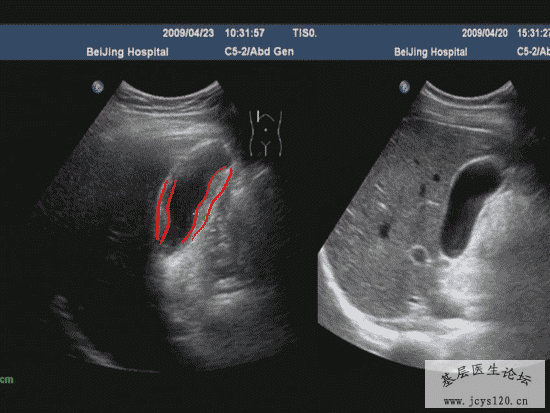

医学教育网讲义里面的精彩图片!